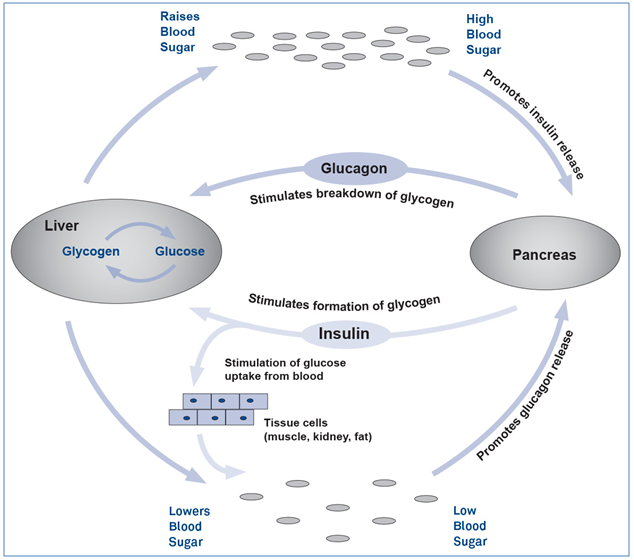

Glucagon plays a role in maintaining a normal concentration of glucose in the blood and it counteracts the effect of insulin in glucose metabolism regulation.

Figure 1 illustrates how glucagon prevents blood glucose from dropping to dangerous levels by stimulating the conversion of glycogen to glucose in the liver in a process called glycogenolysis. In addition, glucagon inhibits glucose consumption by the liver so that more glucose is able to enter the bloodstream.